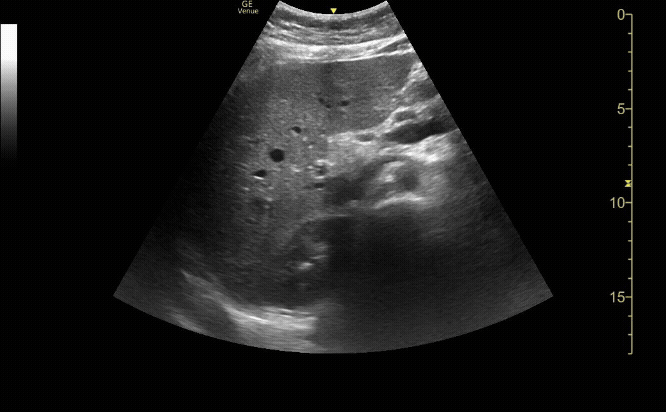

Gallbladder in long view

c/o Alex Alanis, MD